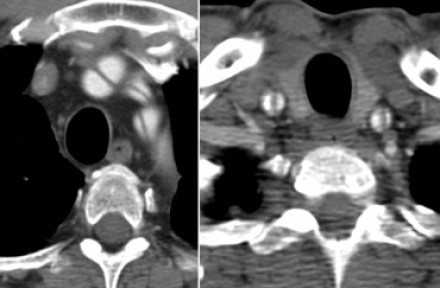

Диссекция брахиоцефальных артерий

- Всегда оцениваете тщательно каждую артерию, отходящую от дуги аорты, на предмет во влечения их в патологический процесс.

![16]()